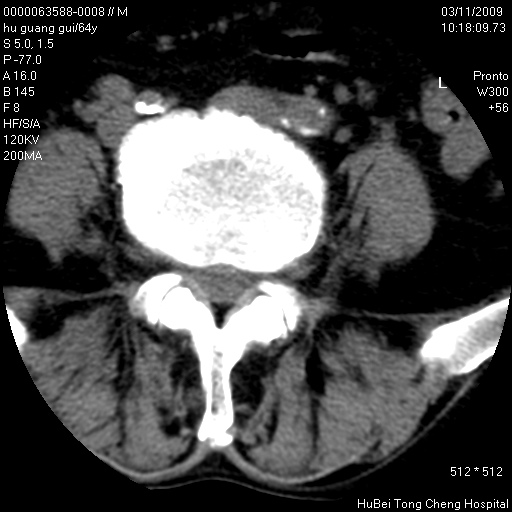

患者 男,64岁。腰痛十余天。(临床未提供其他病史)

临床诊断:腰痛原因待查(腰椎间盘突出症?)。

腰椎间盘ct轴位平扫(层厚5mm,层距4mm),图像如下:

腰椎退行性变,腰4—5椎间盘膨出。

右侧骶骨侧块骨侵蚀,骶髂关节骨性关节面破坏,并见软组织肿块,考虑骨转移瘤可能,进一步检查。

1.腰椎退行性变,腰4—5椎间盘膨出。

2.右侧骶骨侧块骨侵蚀,骶髂关节骨性关节面破坏,并见软组织肿块,考虑:脊索瘤,骨转移瘤可能,进一步检查。

1)腰椎退行性变,l4—5椎间盘膨出。2)骶骨右侧块骨转移瘤可能,3)水平骶椎。建议作一步检查。